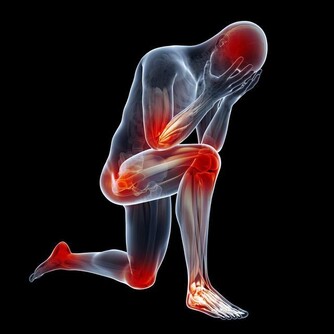

3、乏力沒有食慾

身體告訴我們要好好休息,集中體力對抗進入身體裡的病原菌,往往在這個時候我們會強迫自己吃飯,

吃飯需要消耗能量來消化食物,身體不想吃飯我們就不吃,增加喝水量同時多喝蔬果汁。